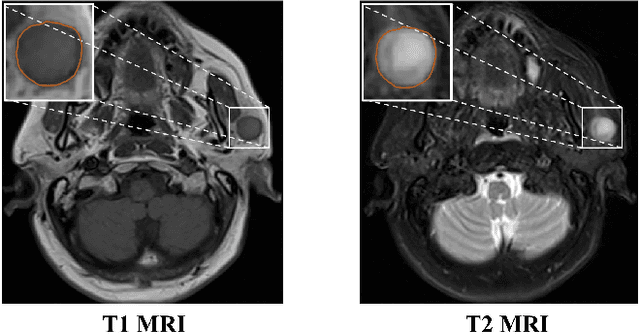

Abstract:Magnetic Resonance Imaging (MRI) plays an important role in diagnosing the parotid tumor, where accurate segmentation of tumors is highly desired for determining appropriate treatment plans and avoiding unnecessary surgery. However, the task remains nontrivial and challenging due to ambiguous boundaries and various sizes of the tumor, as well as the presence of a large number of anatomical structures around the parotid gland that are similar to the tumor. To overcome these problems, we propose a novel anatomy-aware framework for automatic segmentation of parotid tumors from multimodal MRI. First, a Transformer-based multimodal fusion network PT-Net is proposed in this paper. The encoder of PT-Net extracts and fuses contextual information from three modalities of MRI from coarse to fine, to obtain cross-modality and multi-scale tumor information. The decoder stacks the feature maps of different modalities and calibrates the multimodal information using the channel attention mechanism. Second, considering that the segmentation model is prone to be disturbed by similar anatomical structures and make wrong predictions, we design anatomy-aware loss. By calculating the distance between the activation regions of the prediction segmentation and the ground truth, our loss function forces the model to distinguish similar anatomical structures with the tumor and make correct predictions. Extensive experiments with MRI scans of the parotid tumor showed that our PT-Net achieved higher segmentation accuracy than existing networks. The anatomy-aware loss outperformed state-of-the-art loss functions for parotid tumor segmentation. Our framework can potentially improve the quality of preoperative diagnosis and surgery planning of parotid tumors.

Abstract:Parotid gland tumors account for approximately 2% to 10% of head and neck tumors. Preoperative tumor localization, differential diagnosis, and subsequent selection of appropriate treatment for parotid gland tumors is critical. However, the relative rarity of these tumors and the highly dispersed tissue types have left an unmet need for a subtle differential diagnosis of such neoplastic lesions based on preoperative radiomics. Recently, deep learning methods have developed rapidly, especially Transformer beats the traditional convolutional neural network in computer vision. Many new Transformer-based networks have been proposed for computer vision tasks. In this study, multicenter multimodal parotid gland MRI images were collected. The Swin-Unet which was based on Transformer was used. MRI images of STIR, T1 and T2 modalities were combined into a three-channel data to train the network. We achieved segmentation of the region of interest for parotid gland and tumor. The DSC of the model on the test set was 88.63%, MPA was 99.31%, MIoU was 83.99%, and HD was 3.04. Then a series of comparison experiments were designed in this paper to further validate the segmentation performance of the algorithm.

Abstract:Recent works on Multimodal 3D Computer-aided diagnosis have demonstrated that obtaining a competitive automatic diagnosis model when a 3D convolution neural network (CNN) brings more parameters and medical images are scarce remains nontrivial and challenging. Considering both consistencies of regions of interest in multimodal images and diagnostic accuracy, we propose a novel mutual attention-based hybrid dimensional network for MultiModal 3D medical image classification (MMNet). The hybrid dimensional network integrates 2D CNN with 3D convolution modules to generate deeper and more informative feature maps, and reduce the training complexity of 3D fusion. Besides, the pre-trained model of ImageNet can be used in 2D CNN, which improves the performance of the model. The stereoscopic attention is focused on building rich contextual interdependencies of the region in 3D medical images. To improve the regional correlation of pathological tissues in multimodal medical images, we further design a mutual attention framework in the network to build the region-wise consistency in similar stereoscopic regions of different image modalities, providing an implicit manner to instruct the network to focus on pathological tissues. MMNet outperforms many previous solutions and achieves results competitive to the state-of-the-art on three multimodal imaging datasets, i.e., Parotid Gland Tumor (PGT) dataset, the MRNet dataset, and the PROSTATEx dataset, and its advantages are validated by extensive experiments.

Abstract:Over the past decade, convolutional neural networks (CNN) have shown very competitive performance in medical image analysis tasks, such as disease classification, tumor segmentation, and lesion detection. CNN has great advantages in extracting local features of images. However, due to the locality of convolution operation, it can not deal with long-range relationships well. Recently, transformers have been applied to computer vision and achieved remarkable success in large-scale datasets. Compared with natural images, multi-modal medical images have explicit and important long-range dependencies, and effective multi-modal fusion strategies can greatly improve the performance of deep models. This prompts us to study transformer-based structures and apply them to multi-modal medical images. Existing transformer-based network architectures require large-scale datasets to achieve better performance. However, medical imaging datasets are relatively small, which makes it difficult to apply pure transformers to medical image analysis. Therefore, we propose TransMed for multi-modal medical image classification. TransMed combines the advantages of CNN and transformer to efficiently extract low-level features of images and establish long-range dependencies between modalities. We evaluated our model for the challenging problem of preoperative diagnosis of parotid gland tumors, and the experimental results show the advantages of our proposed method. We argue that the combination of CNN and transformer has tremendous potential in a large number of medical image analysis tasks. To our best knowledge, this is the first work to apply transformers to medical image classification.